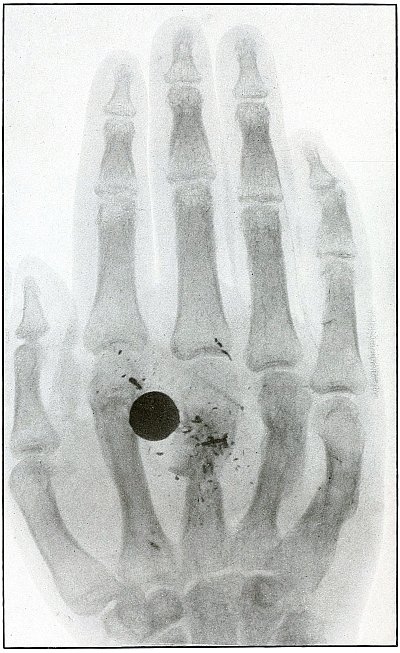

Plate 43.

_

[Pg 97]

Rifle—Plate 43.

UPPER EXTREMITY.

Gunshot Fracture of the Metacarpus.

Wound of entrance, inner aspect of the hand over proximal end of the fifth metacarpal.

Wound of exit, on the outer border of the hand over the distal end of the second metacarpal.

The velocity of the bullet was in mid or long range, as it displaced no fragments, and as it made a point of entrance and exit about the same in appearance.

The wound was infected, which is more frequently the case in the hand than in the forearm.

The treatment is conservative with free incision and drainage in the management of infection. [Pg 98]